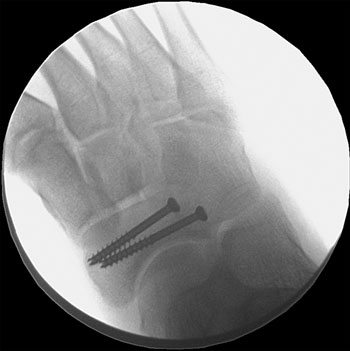

Some stress fractures require surgery to heal properly. In most cases, this involves supporting the bones by inserting a type of fastener. This is called internal fixation. Pins, screws, and/or plates are most often used to hold the small bones of the foot and ankle together during the healing process.

A00379F03.jpg" title="This x-ray of the mid-foot shows screws placed in the navicular bone to keep the fracture in a fixed position during healing." credit="Reproduced with permission from Shindle MK, Endo Y, Warren RF, Lane JM, Helfet DL, Schwartz EN, Ellis SJ: Stress fractures about the tibia, foot, and ankle. J Am Acad Orthop Surg March 2012 vol. 20 no. 3 167-176.">In most cases, it takes from 6 to 8 weeks for a stress fracture to heal. More serious stress fractures can take longer. Although it can be hard to be sidelined with an injury, returning to activity too soon can put you at risk for larger, harder-to-heal stress fractures and an even longer down time. Reinjury could lead to chronic problems and the stress fracture might never heal properly.

This x-ray of the mid-foot shows screws placed in the navicular bone to keep the fracture in a fixed position during healing.

Reproduced with permission from Shindle MK, Endo Y, Warren RF, Lane JM, Helfet DL, Schwartz EN, Ellis SJ: Stress fractures about the tibia, foot, and ankle. J Am Acad Orthop Surg March 2012 vol. 20 no. 3 167-176.